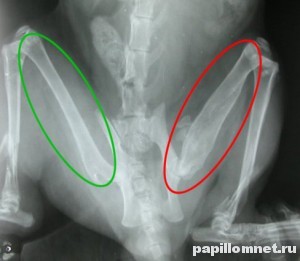

Рентгеновский снимок отлично показывает весь процесс формирования подобного новообразования. Оно выглядит подобно облачку, появившемуся в области перелома кости. Костная мозоль образуется организмом человека в случае перелома кости для того, чтобы восстановить ее целостность. Происходит это постепенно.

Лечением перелома занимаются специалисты-травматологи, которые, взглянув на рентгеновский снимок перелома, могут сразу определить, запущенная стадия или травма еще «свежая». Именно присутствие мозоли в области перелома служит явным показателем того, что кость сломана достаточно давно и уже начинает срастаться.